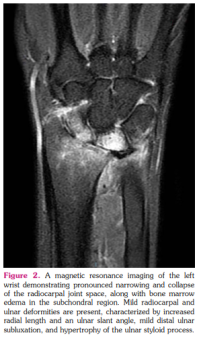

An X-ray of the left wrist (Figures 1a, b) revealed significant narrowing and collapse of the radiocarpal joint space, accompanied by surface irregularities, subchondral sclerosis, and subchondral cyst formation. No posttraumatic bone fractures were detected, and the soft tissues appeared normal. Subsequent imaging with MRI showed a further increase in the pronounced narrowing and collapse of the radiocarpal joint space, along with bone marrow edema in the subchondral region. Osteophytes were detected, along with subchondral cystic changes. Notably, marked synovitis was observed in the radiocarpal and distal radial ulnar joints. Mild radiocarpal and ulnar deformity was present, characterized by increased radial length and an ulnar slant angle, mild distal ulnar subluxation, and hypertrophy of the ulnar styloid process, consistent with the features of Madelung's deformity (Figure 2).

Plain X-rays can detect pathognomonic findings for Madelung’s deformity (Table 1).[7] The patient presented in this case had a severe form of Madelung’s deformity. Although advanced imaging are not necessary to confirm the diagnosis, an MRI delineates three-dimensional deformity, the extent of growth plate involvement, and the presence of a Vickers ligament.[8]